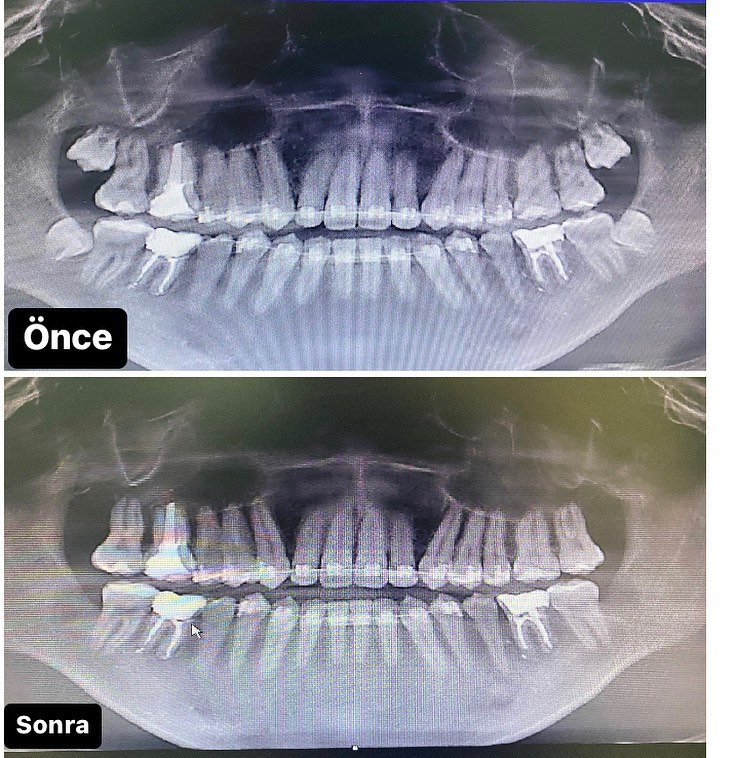

İmplant rentgenləri